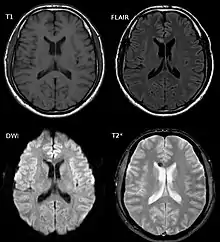

Diffuse axonal injury after a motorcycle accident. MRI after 3 days: on T1-weighted images the injury is barely visible. On the FLAIR, DWI and T2*-weighted images a small bleed is identifiable.

DAI is difficult to detect since it does not show up well on CT scans or with other macroscopic imaging techniques, though it shows up microscopically.[9] However, there are characteristics typical of DAI that may or may not show up on a CT scan. Diffuse injury has more microscopic injury than macroscopic injury and is difficult to detect with CT and MRI, but its presence can be inferred when small bleeds are visible in the corpus callosum or the cerebral cortex.[34] MRI is more useful than CT for detecting characteristics of diffuse axonal injury in the subacute and chronic time frames.[35] Newer studies such as Diffusion Tensor Imaging are able to demonstrate the degree of white matter fiber tract injury even when the standard MRI is negative. Since axonal damage in DAI is largely a result of secondary biochemical cascades, it has a delayed onset, so a person with DAI who initially appears well may deteriorate later. Thus injury is frequently more severe than is realized, and medical professionals should suspect DAI in any patients whose CT scans appear normal but who have symptoms like unconsciousness.[9]

MRI is more sensitive than CT scans, but is still liable to false negatives because DAI is identified by looking for signs of edema, which may not always be present.[33]